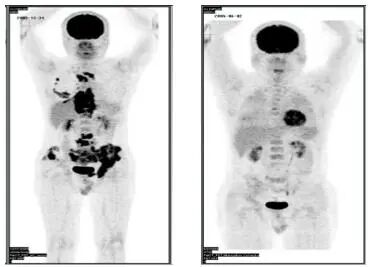

淋巴瘤化疗前后对比